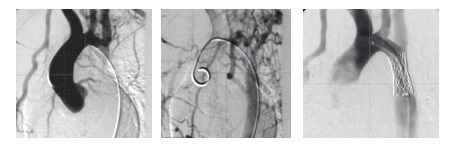

Jak brzmi ostateczne rozpoznanie i zastosowana metoda leczenia?

Wskaż prawidłowy opis angiografii i zastosowaną metodę leczenia: